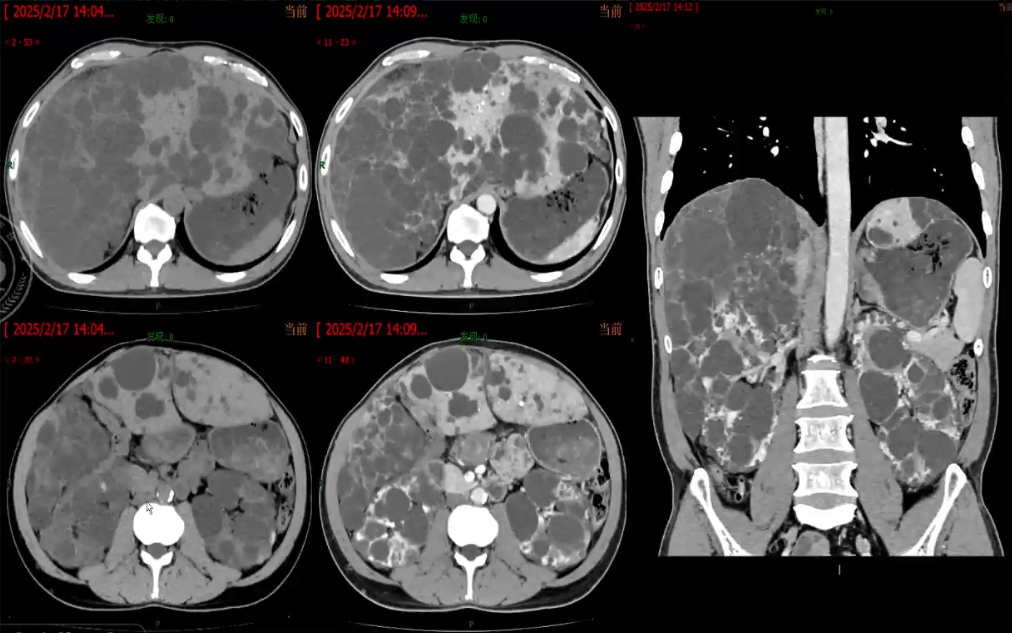

多囊肝

> 是一种常染色体显性遗传病变,分为常染色体显性多囊肾病型、单纯性常染色体显性多囊肝病型

> 常染色体显性多囊肾病型,多见,常染色体显性多囊肾病合并肝脏受累,由PKD1或PKD2基因突变导致,常合并多囊肾

> 单纯性常染色体显性多囊肝病型,由PRKCSH或SEC63等基因突变引起,仅累及肝脏

> 肝内布满多发、弥漫、数量众多的不同大小囊肿(>20个),可累及全肝,也可密集于一叶(肝右叶较多)囊肿大小不等,有融合趋势,易继发出血或感染

> 肝脏通常增大,由于肝脏肿大的占位效应,邻近器官及肝内主要血管受压的情况较为常见

影像表现

> 由多个融合囊肿形成的“多房样”表现病灶

> 囊肿内含清亮或淡黄色液体,其CT值和MR信号强度分别与水的特征一致,平扫CT显示囊内密度增高或MR T1WI信号增高,可能提示囊肿内出血或感染

> 囊壁菲薄且规则,无强化表现